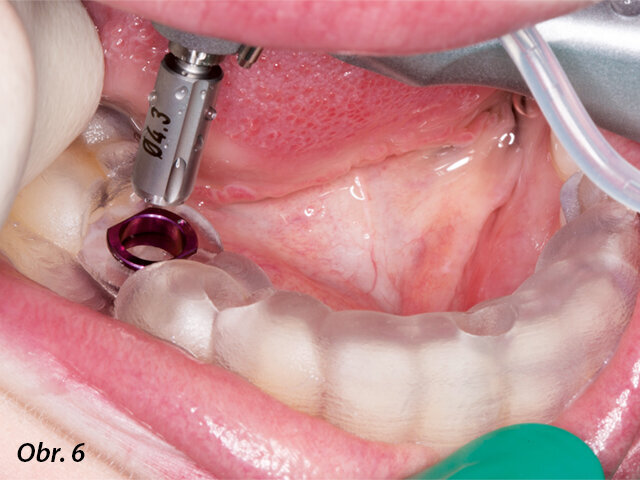

K dosažení přesně naplánované pozice implantátu byla zhotovena chirurgická šablona. Dr. Lindroos podle svých slov dává ve většině implantologických případů přednost řízené chirurgii, protože tak lze zaručit zavedení implantátu v optimální pozici a zkrátit dobu zákroku, stejně jako dobu hojení.

V tomto případě byla chirurgická šablona navržena pomocí modulu Planmeca Romexis 3D Implant Guide. Šablona pak byla vytištěna na 3D tiskárně Planmeca ProModel, což jsou technologie, které umožňují výrobu individualizovaných implantologických a chirurgických šablon pro náročné chirurgické procedury a plánování ošetření.

Chirurgická fáze zavádění implantátu byla provedena pomocí chirurgické šablony vytištěné na 3D tiskárně.